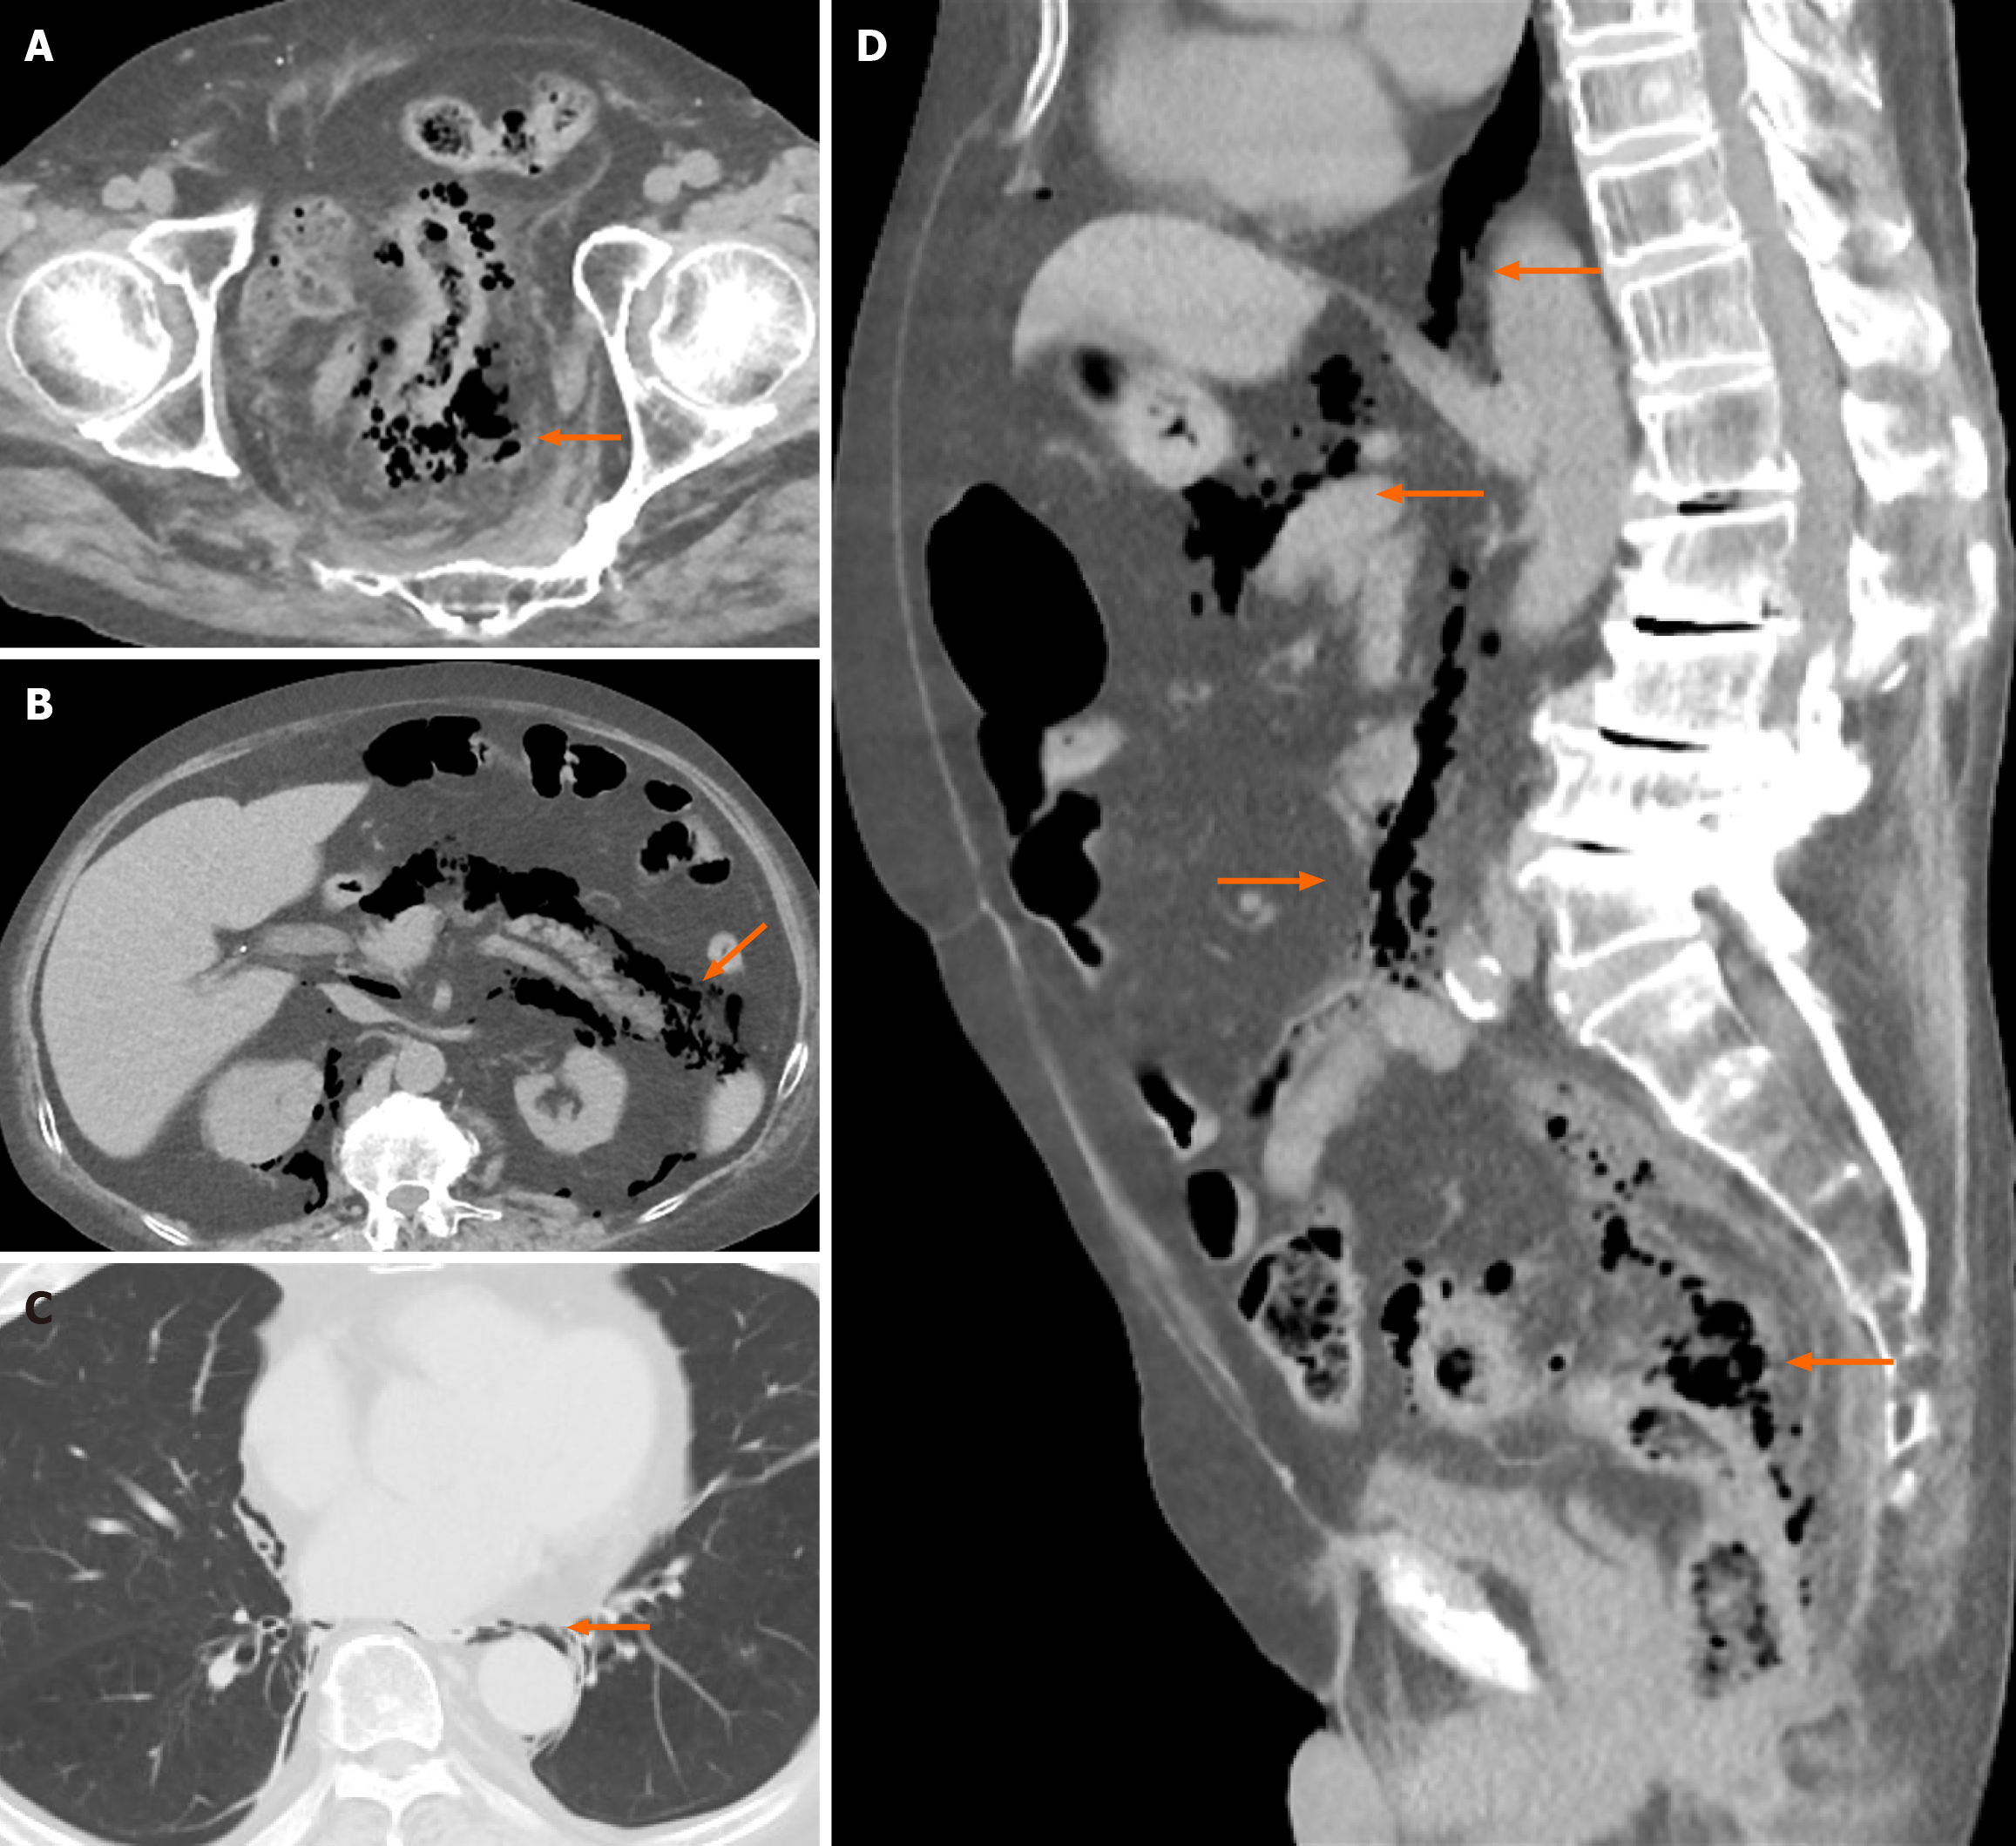

Abdominal computed tomography (CT) was performed with intravenous contrast. Axial, sagittal and coronal reconstructions were obtained. The CT examination revealed mural changes including focal wall thickening and edematous changes at the rectosigmoid junction. The extramural findings were peripheral fat stranding around the affected segment, diffuse pneumoretroperitoneum around the pancreas and kidneys, minor pneumoperitoneum, and pneumomediastinum (Figure 1).

Perforated sigmoid colon diverticulitis with pneumoperitoneum, pneumoretroperitoneum, and pneumomediastinum. The CT findings indicated that the case corresponded to Hinchey stage II and was most consistent with WSES stage 2B complicated diverticulitis.